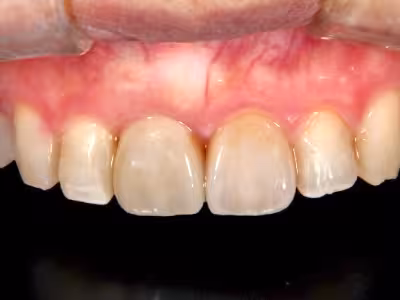

治療前

治療後

40代・女性

来院理由

前歯で噛むと痛む/見た目も気になる

治療内容

- ① CT診査・サージカルガイド作製

- ② 抜歯と同時にインプラント埋入(抜歯即時埋入)+結合組織移植

- ③ ホワイトニング

- ④ セラミッククラウン装着

治療期間

約6 か月(手術当日+3回の経過観察・最終補綴)

費用

1,320,000円(税込・自費診療、保険適用外)

リスク・副作用

- 術後の腫脹・疼痛・出血

- インプラントが骨結合しない可能性

医院コメント

噛む機能だけでなく口元のバランスも改善。

定期メンテナンスにより長期安定を目指します。